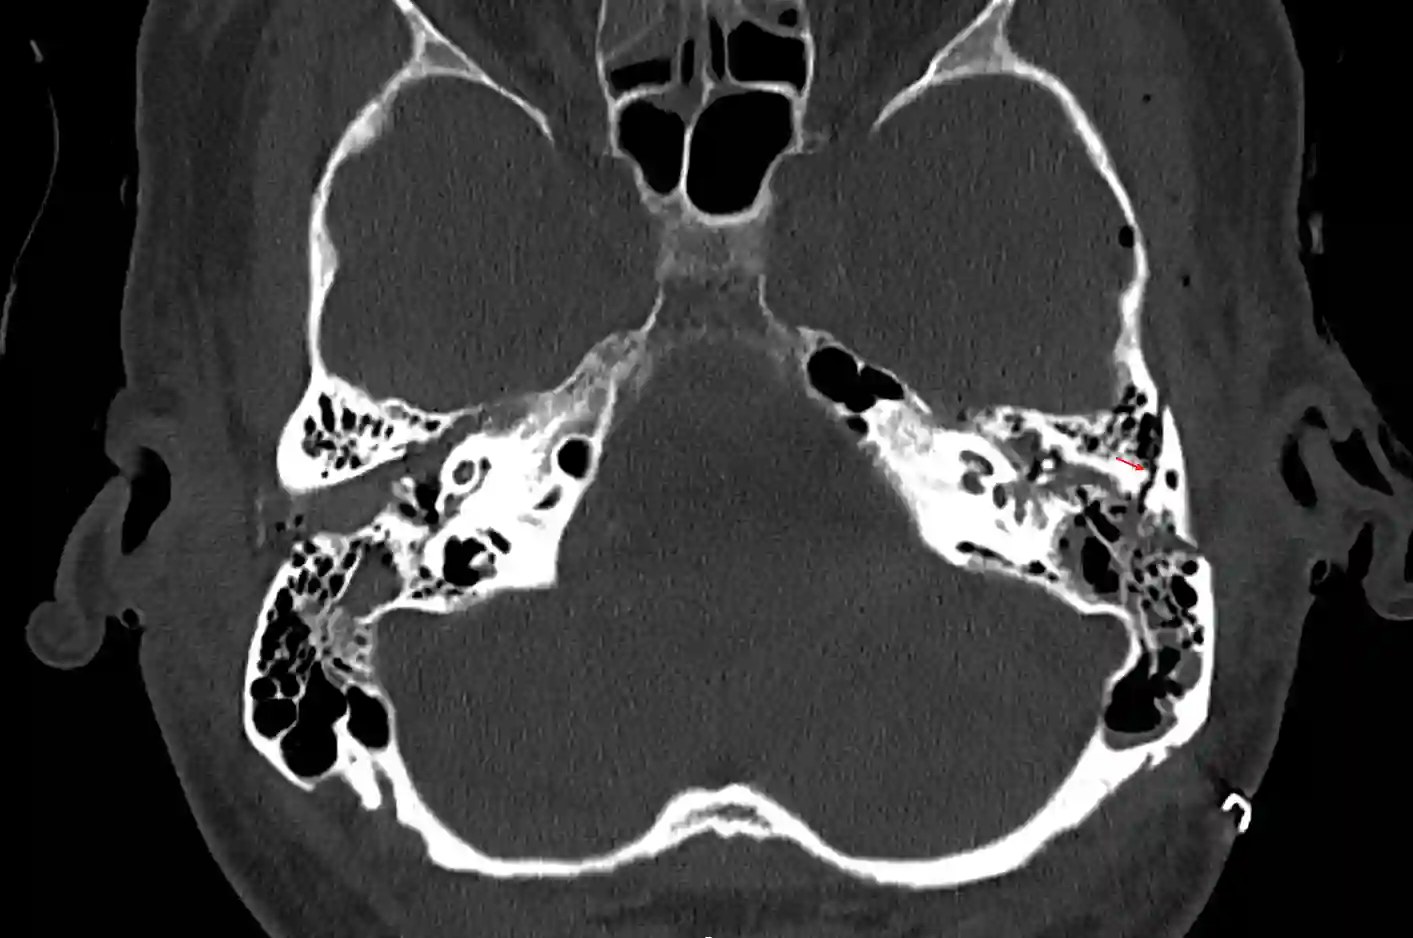

Darstellung einer Felsenbeinquerfraktur (roter Pfeil) in einer axialen CT Bildgebung.